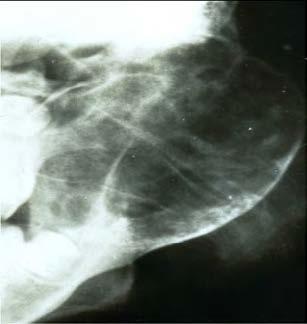

What does this person have?

This is a Aneurysmal Bone Cysts